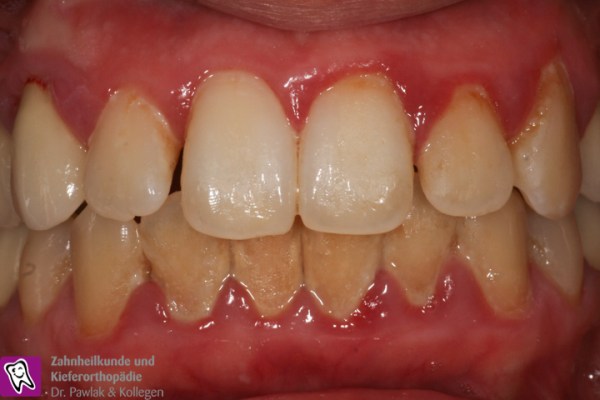

Frontzahnbereich vor Parodontitis-Behandlung mit entzündetem Zahnfleisch. Frontzahnbereich nach Parodontitis-Behandlung mit gesundem Zahnfleisch.